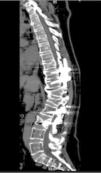

Tomografía computarizada de columna vertebral, corte sagital, en la que se evidencian tornillos transpediculares en vértebras torácicas 10 – 11 y lumbares L2 – L3; hipercifosis residual a nivel de fractura por acuñamiento en los cuerpos vertebrales T12-L1; disminución de la altura del cuerpo vertebral L3; espondilosis de columna torácica y lumbar y disminución de la matriz ósea.

Mediante la imagen se confirmó fractura de los cuerpos vertebrales, por lo que el servicio de Neurocirugía consideró necesario realizar una nueva intervención quirúrgica en donde se cambió el material de artrodesis y se usó metilmetacrilato para la fijación de los materiales protésicos utilizados durante la misma, esto dado por la disminución de la densidad ósea vertebral.